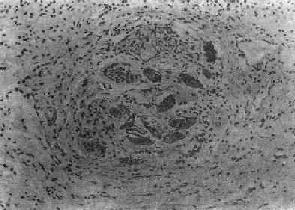

(1)急性虫卵结节:肉眼观为灰黄色、粟粒至绿豆大(0.5~4mm)的小结节。镜下见结节中央常有1~2个成熟虫卵,也偶可多达20个以上。这些成熟虫卵的卵壳上附有放射状嗜酸性的棒状体,也称为Hoeppli现象,用免疫荧光法已证实为抗原抗体复合物。虫卵周围是一片无结构的颗粒状坏死物质及大量嗜酸性粒细胞浸润。因其病变类似脓肿,故也称为嗜酸性脓肿(图19-5)。在坏死组织中可混杂多数菱形或多面形屈光性蛋白质晶体,即Charcot-Leyden结晶,系嗜酸性粒细胞的嗜酸性颗粒互相融合而成。随后虫卵周围产生肉芽组织层,其中有以嗜酸性粒细胞为主的炎症细胞浸润,还有单核巨噬细胞、淋巴细胞、浆细胞及少量中性粒细胞。随着病程的发展,肉芽组织层逐渐向虫卵结节中央生长,并出现围绕结节呈放射状排列的类上皮细胞层。类上皮细胞层逐渐加宽,嗜酸性粒细胞显著减少,构成晚期急性虫卵结节(图19-6),这是向慢性虫卵结节发展的过渡阶段。

肝血吸虫病之急性虫卵结节

图19-5 肝血吸虫病之急性虫卵结节

结节中心有一成熟虫卵,卵壳表面可见放射状物质,周围广泛坏死伴大量嗜酸性粒细胞浸润